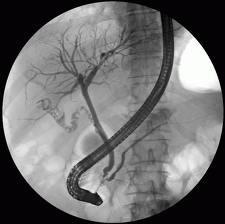

ERCP nin şematik görünümü

Tek aşamalı işlemin radyolojik görünümü